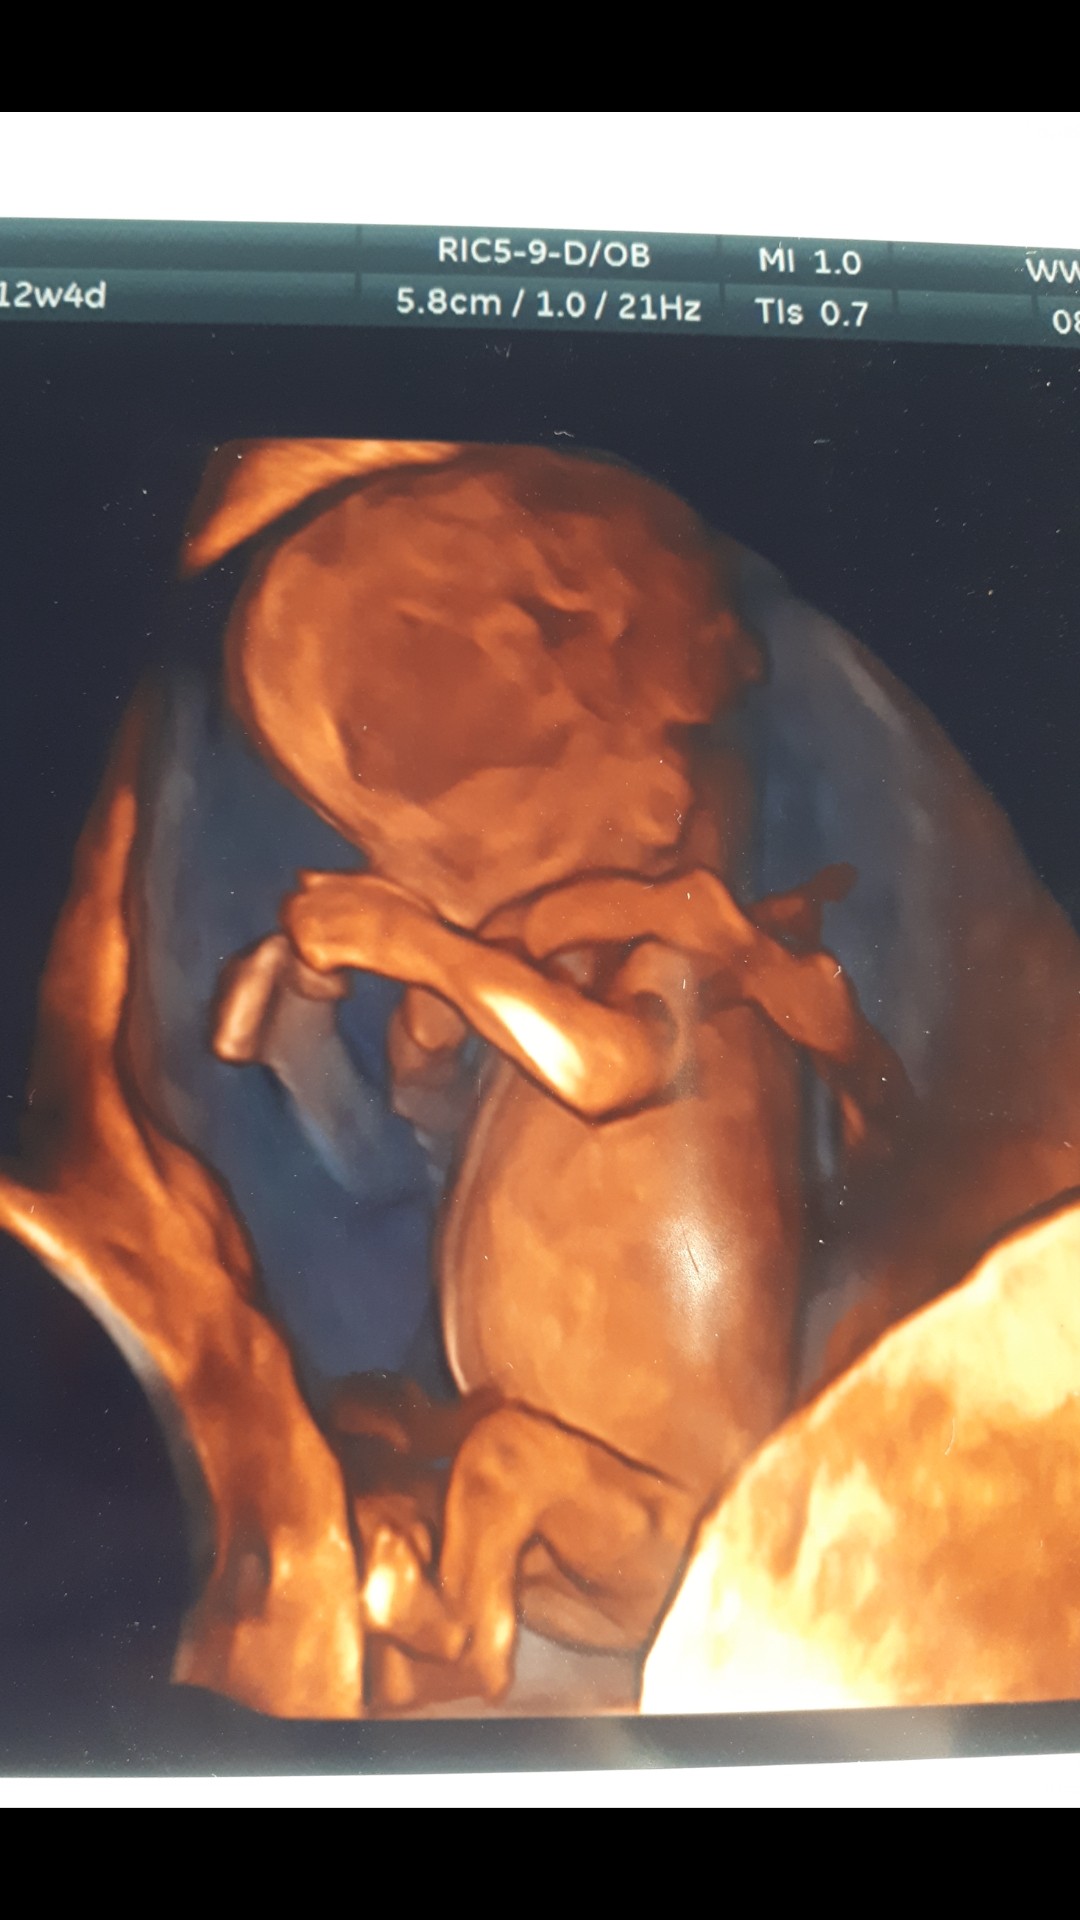

Ja po wizycie kontrolnej;) wszystko super;) I dostałam takie zdjecie😁 jak dla mnie trochę straszne😅🙈

20211021_114004.jpg